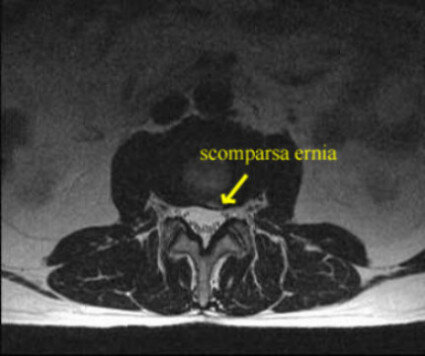

A distanza di un anno eseguiva risonanza magnetica, con completa scomparsa del frammento erniario.

La regressione di un ernia discale può essere un fenomeno naturale e spontaneo. In questo caso non è scientificamente dimostrabile il rapporto con l’ozonoterapia sull’ottima evoluzione radiologica.